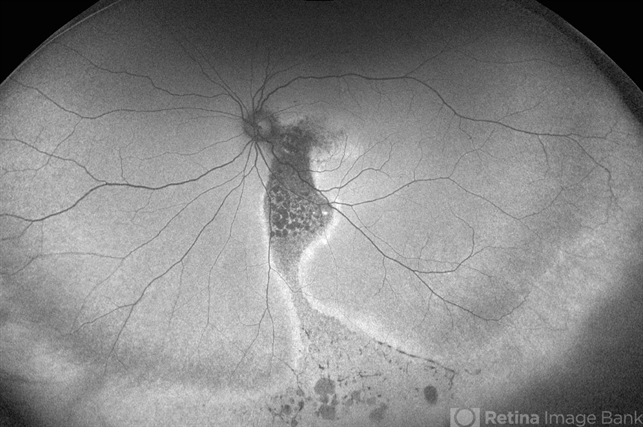

- central serous chorioretinopathy (CSCR)

- Fundus Autofluorescence imaging of an 59-year-old man with Chronic Central Serous Chorioretinopathy demonstrating a Comet Tail Sign.